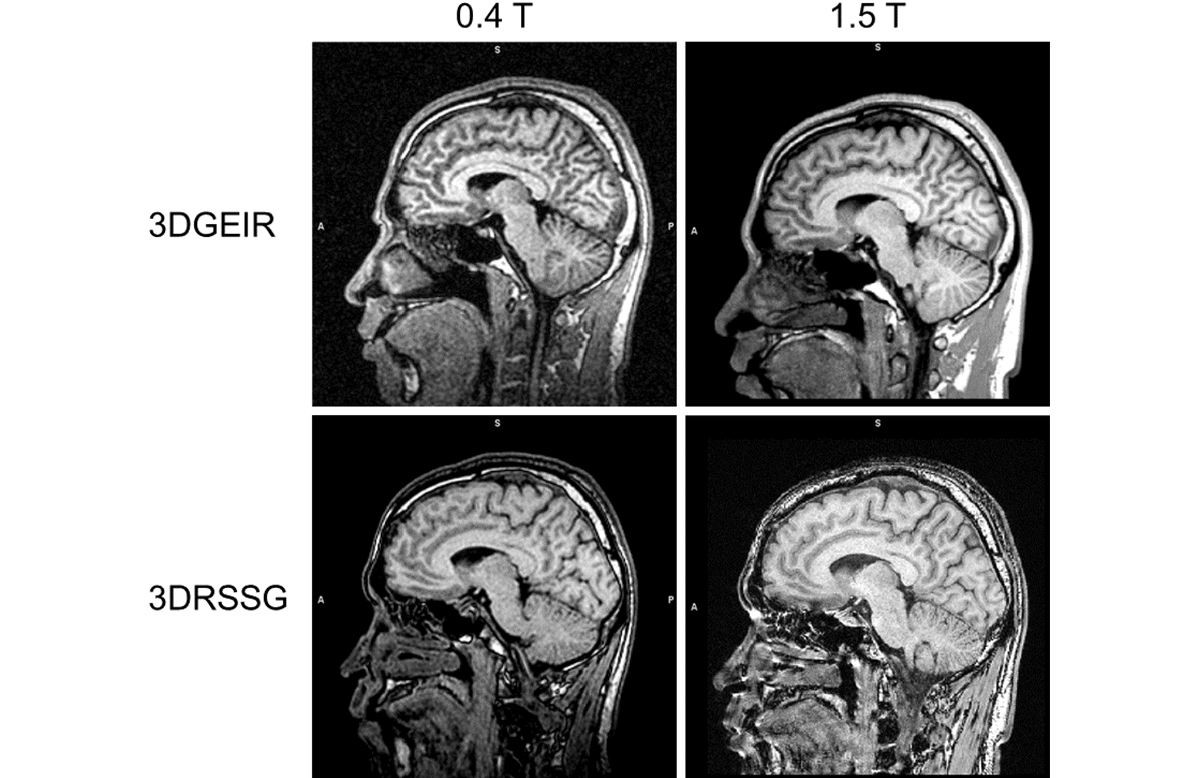

この最適化した撮像シーケンス・パラメータを使用し、同一ボランティアで0.4テスラ装置(APERTO Lucent*1)と1.5テスラ装置(ECHELON OVAL*2)で3D T1強調画像を撮像した例を図1に示す。VBMで一般的に用いられる組織自動分離抽出結果を利用して灰白質・白質・脳脊髄液の信号コントラストを算出すると、3DGEIRでは0.4テスラのボランティア3例の平均で白質・灰白質コントラストが1.63、脳脊髄液・灰白質コントラストが0.33となり、小数例での検討ではあるが1.5テスラの1.39と0.39と比較してむしろ高いコントラストを有することが示された。3DRSSGでは0.4テスラで白質・灰白質コントラストが1.35、脳脊髄液・灰白質コントラストが0.55となり、1.5テスラの同シーケンスではそれぞれ1.29と0.50であったため、ほぼ同等のコントラストが得られていることが確認できた。

図1 同一ボランティアにおける0.4テスラ装置と1.5テスラ装置による3D T1強調画像(上段:3DGEIR、下段:3DRSSG)